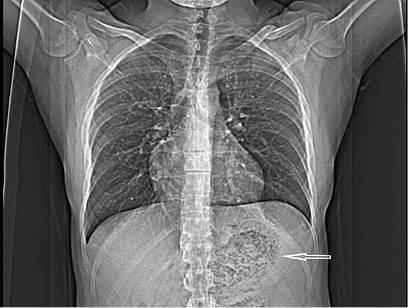

A thirty two years old male patient presented to our surgery department with complain of postprandial abdominal pain, early satiety and occasional vomiting episodes. He lost 5–6 kg in the past 6 months. The symptoms were present for the last 1 year. No comorbidity was reported. Previously he underwent a gastroscopy in another hospital where a stomach bezoar and large ulcer was diagnosed (Figure 1). Plain x-ray (Figure 2), computerized tomography (CT) scan (Figures 3 and 4) and gastroscopy were conducted in our institution. The gastroscopic examination reported giant rough bezoar impossible for endoscopic retrieval.

plain-2.jpg

Figure 2. Plain chest x-ray with visible mass in the stomach